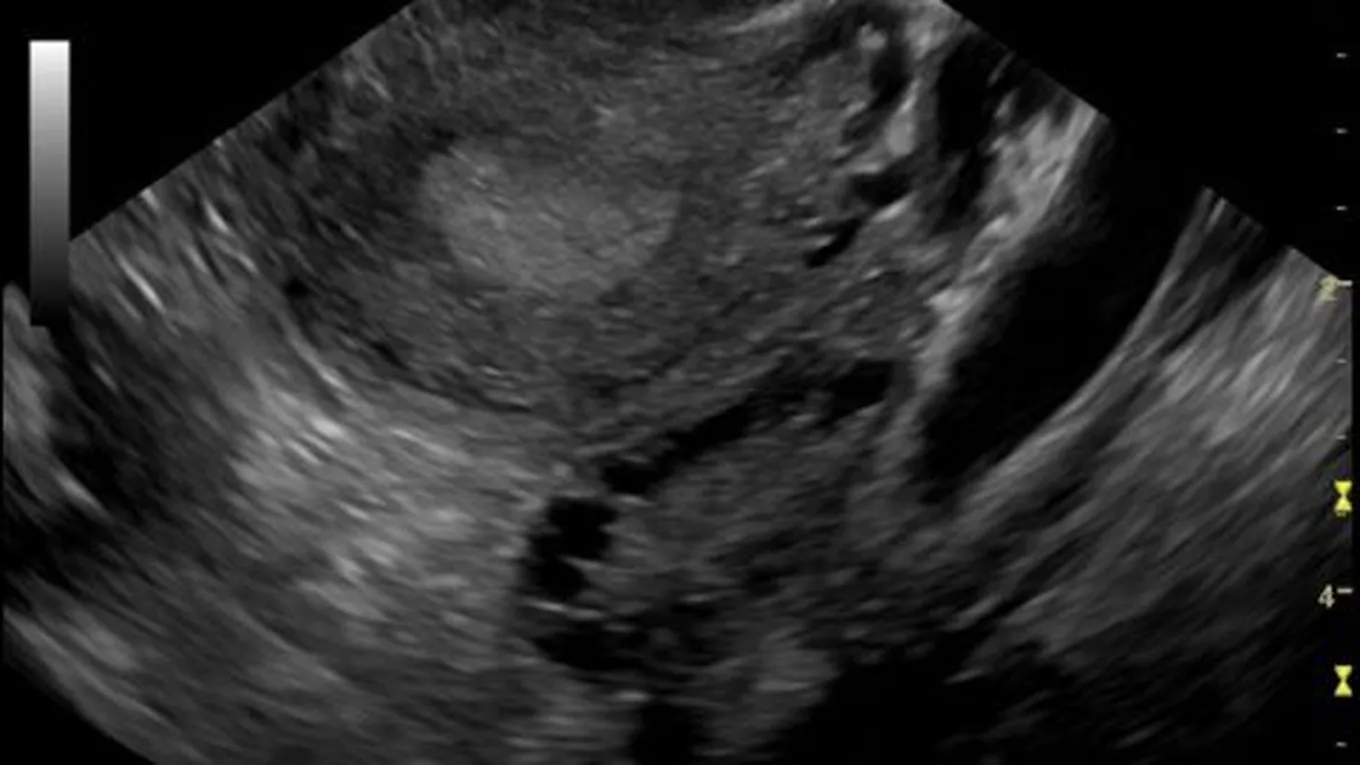

آثار تكيس المبايض على الحمل

آثار تكيس المبايض على الخصوبةيمكن أن تعاني النساء المصابات بمتلازمة المبيض متعدد الكيسات (بالإنجليزية: Polycystic ovarian syndrome) التي تُعرف أيضاً بتكيس

يمكن أن تعاني النساء المصابات بمتلازمة المبيض متعدد الكيسات (بالإنجليزية: Polycystic ovarian syndrome) التي تُعرف أيضاً بتكيس المبايض بمواجهة صعوبة في الحمل، ويُعزى ذلك حقيقةً إلى ارتفاع مستوى الهرمونات في الجسم، والتي تحول دون إتمام عملية الإباضة على الوجه المطلوب، ولذلك تُنصح السيدات اللاتي يُعانين من هذه المشكلة بممارسة التمارين الرياضية، وتناول الطعام الصحيّ، وإنقاص الوزن الزائد، فهذه السلوكيات من شأنها أن تساعد على علاج المشكلة.[1]